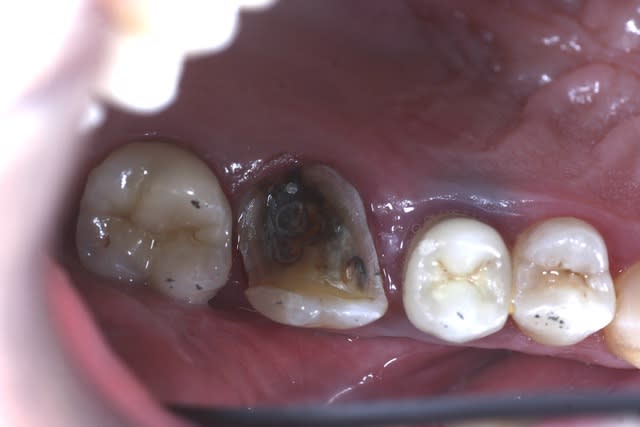

Je ne vois pas quand un onlay n'est pas indiqué ?

Même quand il ne reste rien, la preuve ci-dessous.